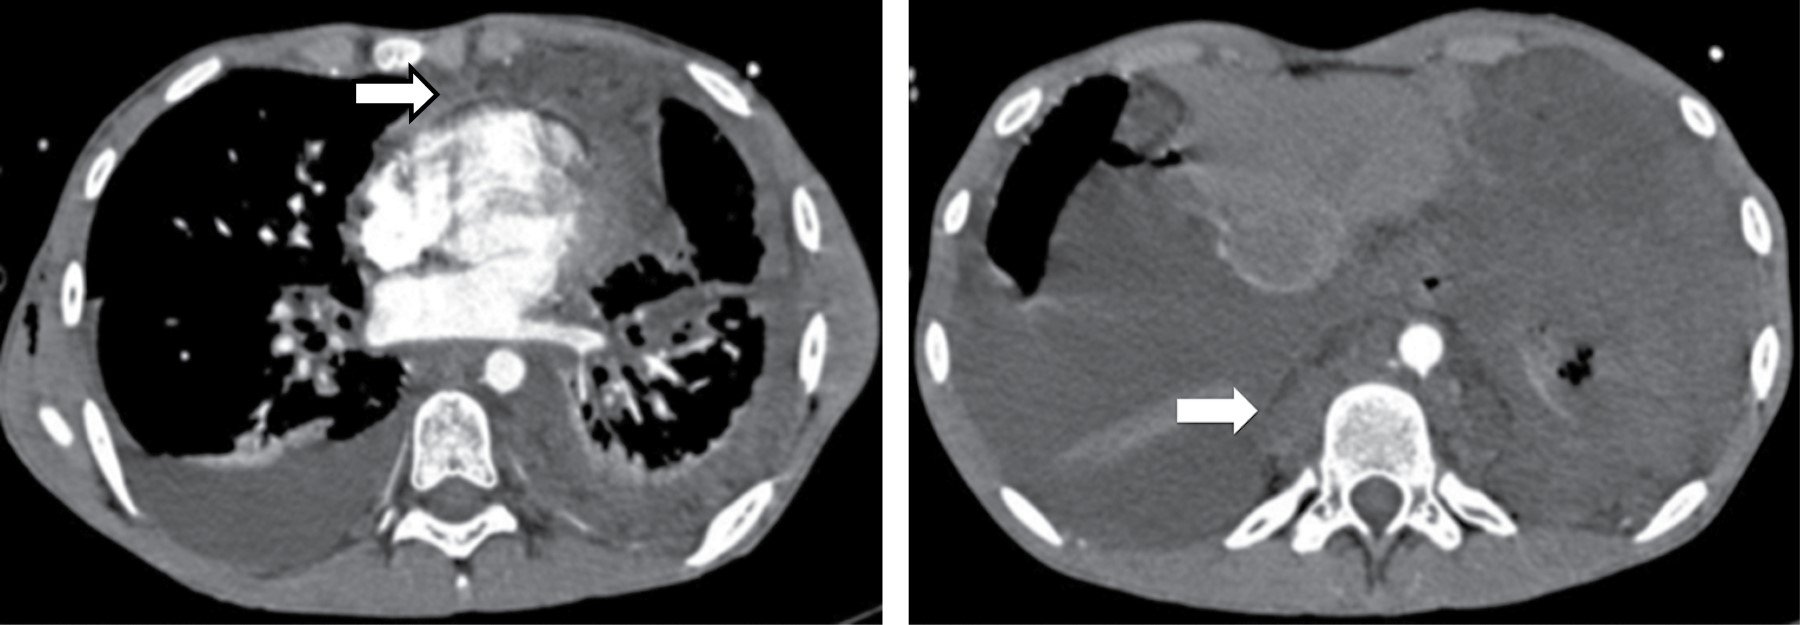

Representa una colección encapsulada de secreciones pancreáticas, sangre y material necrótico. Siempre ocurre en la parte inferior de mediastino posterior, ganando acceso del tórax por la vía de hiato esofágico o aórtico. La tomografía muestra un quiste de pared delgada, baja atenuación en el mediastino posterior o adyacente a la cavidad torácica asociado con compresión o desplazamiento del esófago, pueden ser hiperatenuantes dependiendo de si hay hemorragia o infección (Figura 12).